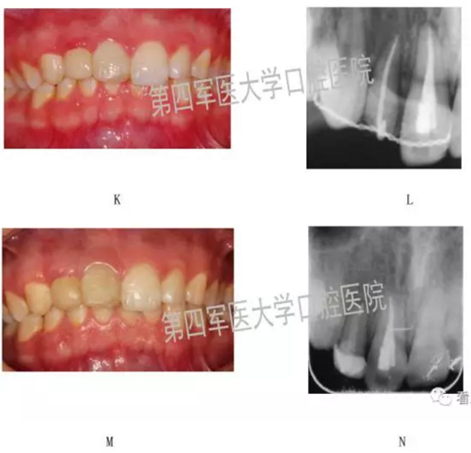

四、典型病例: